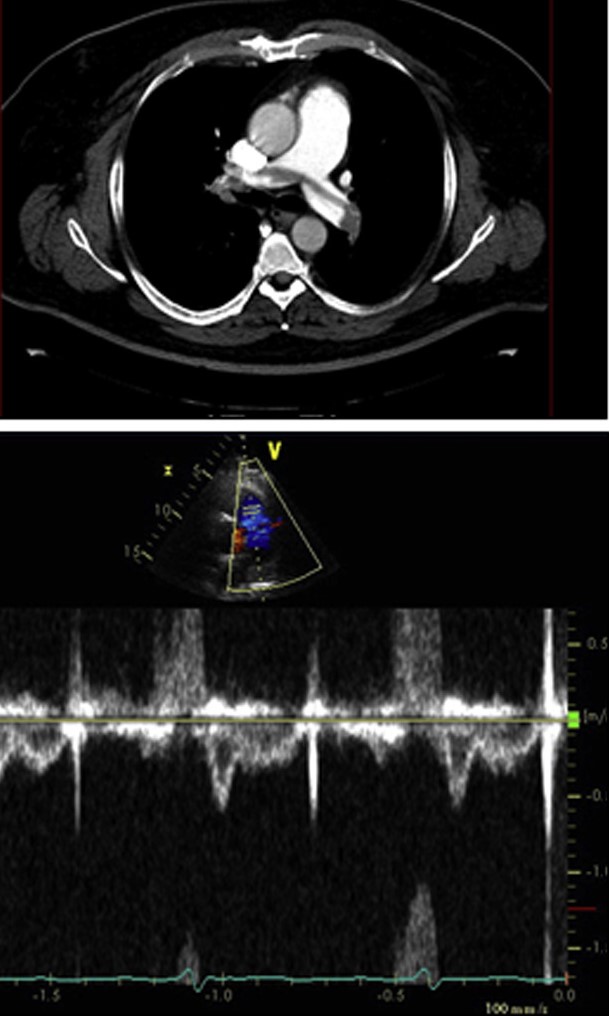

Incredibly pleased to share our newest article, now published @JACCJournals (tinyurl.com/3ewvtvhf) led by superstar T32 fellow, @n_spetko, on the distribution of imaging around the US and relationship of distance to imaging and receipt. #Tweetorial to follow. @BidmcCvi